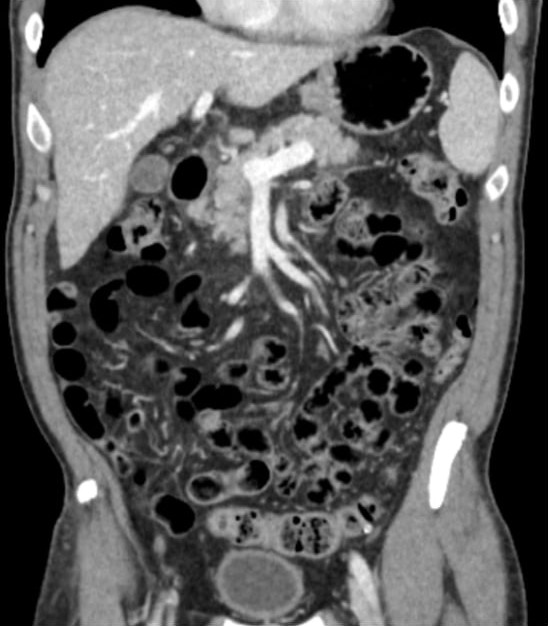

Specifically designed to darken the bowel lumen, creating a high-contrast environment that makes vascularized tissues and tumors pop.

➜ Superior Anatomic Delineation

Clearly distinguishable anatomy

Conventional Positive

Oral Contrast

Similar shades of grey